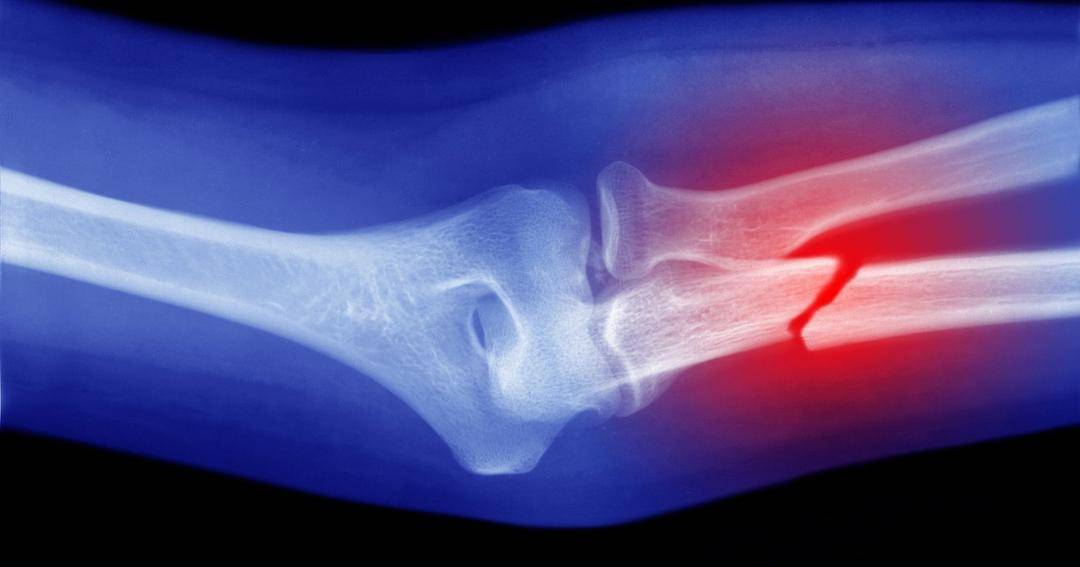

2. Patah tulang

Patah tulang adalah kondisi patahnya tulang yang terjadi karena adanya tekanan atau kekuatan yang tiba-tiba atau sangat kuat. Ini mencakup jatuh, yang memberikan dampak langsung pada tubuh, dan cedera terkait olahraga.

Orang yang berisiko tinggi mengalami patah tulang adalah orang tua, individu dengan osteoporosis dan gangguan endokrin atau usus, dan mereka yang menggunakan kortikosteroid.

Dilansir dari Makati Medical Center, ada beberapa jenis fraktur tetapi biasanya diklasifikasikan sebagai tertutup atau terbuka, dan tidak lengkap atau lengkap. Berikut penjelasannya:

Fraktur tertutup/terbuka

Fraktur tertutup adalah ketika tulang yang patah tidak merusak kulit. Sebaliknya, patah tulang terbuka terjadi ketika ketika ujung tulang yang patah merobek kulit. patah tulang terbuka mengekspos tulang dan jaringan lain ke permukaan, sehingga risiko infeksi menjadi lebih besar.

Fraktur tidak lengkap/lengkap

Fraktur tidak lengkap adalah ketika tulang retak tanpa patah sepenuhnya, menjaganya tetap utuh. Fraktur lengkap, sementara itu, terjadi ketika tulang patah atau hancur menjadi dua bagian atau lebih.

Kedua jenis ini memiliki banyak variasi, tergantung pada bagaimana tulang patah dan kondisinya setelah patah.